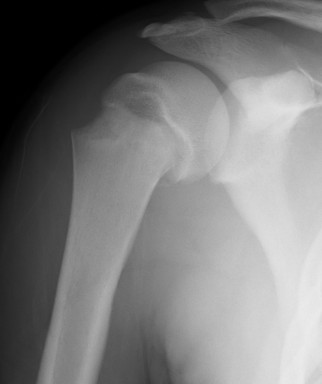

Case: 18 year old boy

Initial xray 18 month xray